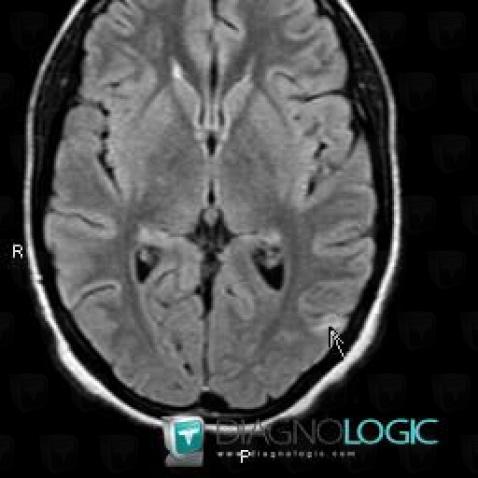

Voici les informations spécifiques à l'image clé ci dessus:

- Diagnostic Tuberculose (lié à Abcès), Localisation(s) Hémisphères cérébraux, comportant les gammes Lésion intracérébrale en hypersignal T2 ou FLAIR

Voici les informations spécifiques à l'image clé ci dessus:

- Diagnostic Tuberculose (lié à Abcès), Localisation(s) Hémisphères cérébraux, comportant les gammes Lésion intracérébrale en hypersignal T2 ou FLAIR